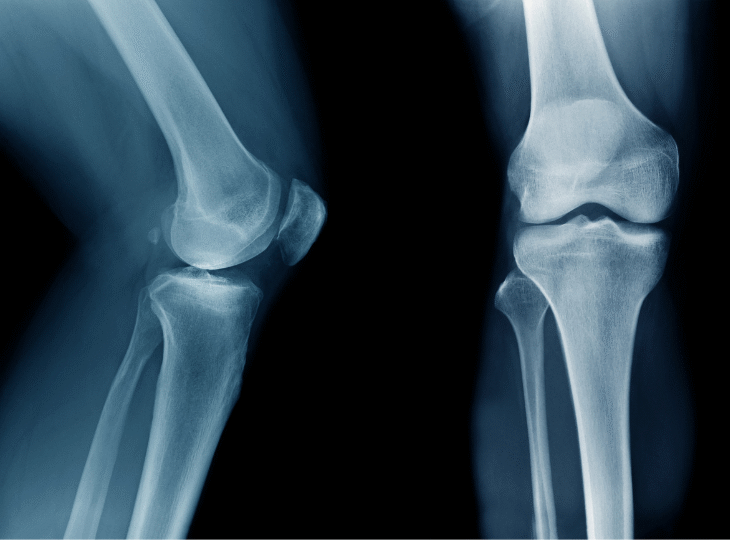

Bone cement is used mainly for hip and knee replacements but also for some shoulder and elbow replacements. Other orthopaedic procedures are unlikely to be affected.